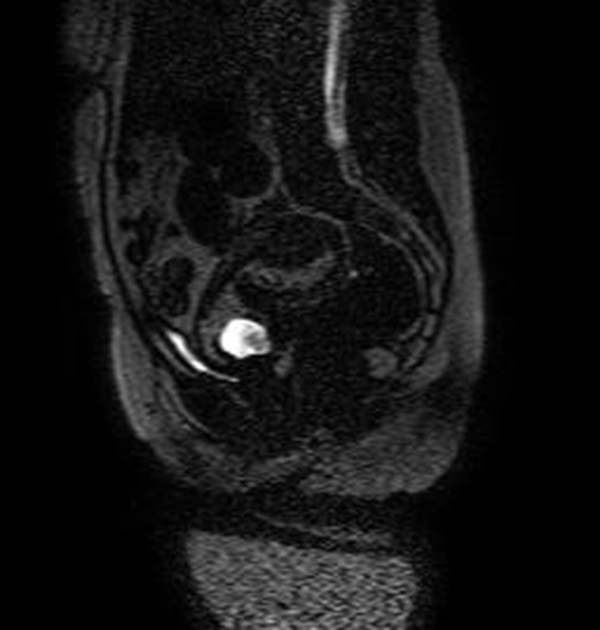

Se realizó una RNM (Philips 1.5 Tesla) que permitió confirmar el diagnóstico de EEC (figuras 5 a 8).

Jung y cols. (28) encontraron como hallazgos en RMN de EEC una masa mal definida con señales muy heterogéneas en T2, hiperintensidades internas e irregulares en T1, con un anillo circunferencial o parcial de baja intensidad de señal, con realce periférico irregular del componente sólido papilar, acompañado de vacíos de señal de morfología tubular. Esto va en concordancia con lo referido por Tamai y cols. (27), que describen típicamente el EEC como una masa hemorrágica, heterogénea y con realce intenso de los componentes papilares del tejido.

Una secuencia útil en la identificación del hematoma reciente es el T2*, que podría remplazar el uso del gadolinio en esta indicación particular. La sensibilidad del 95 % y la especificidad del 100 % de esta secuencia mejora significativamente el desempeño de la resonancia en el diagnóstico de EE (29).

El uso de gadolinio intravenoso incrementa la especificidad en el diagnóstico de embarazo tubárico, lo que permite diferenciar el realce normal de la trompa de un hematoma reciente. En este caso, este principio nos ayudó a delimitar la afectación decidual y a descartar la presencia de un hematoma asociado (30). La resonancia con gadolinio también se ha utilizado en el seguimiento del tratamiento conservador del EEC (31).